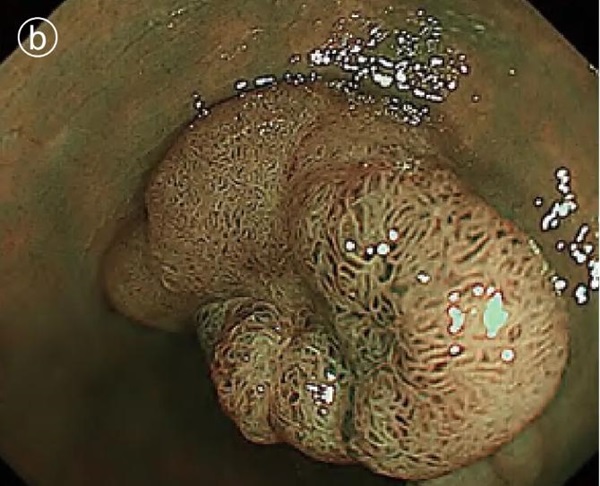

b. Narrow band imaging (NBI) images

c. Spraying indigo carmine to enlarge the image

It was discovered that the depressions that were perceived by conventional observation were actually grooves between the leaves.